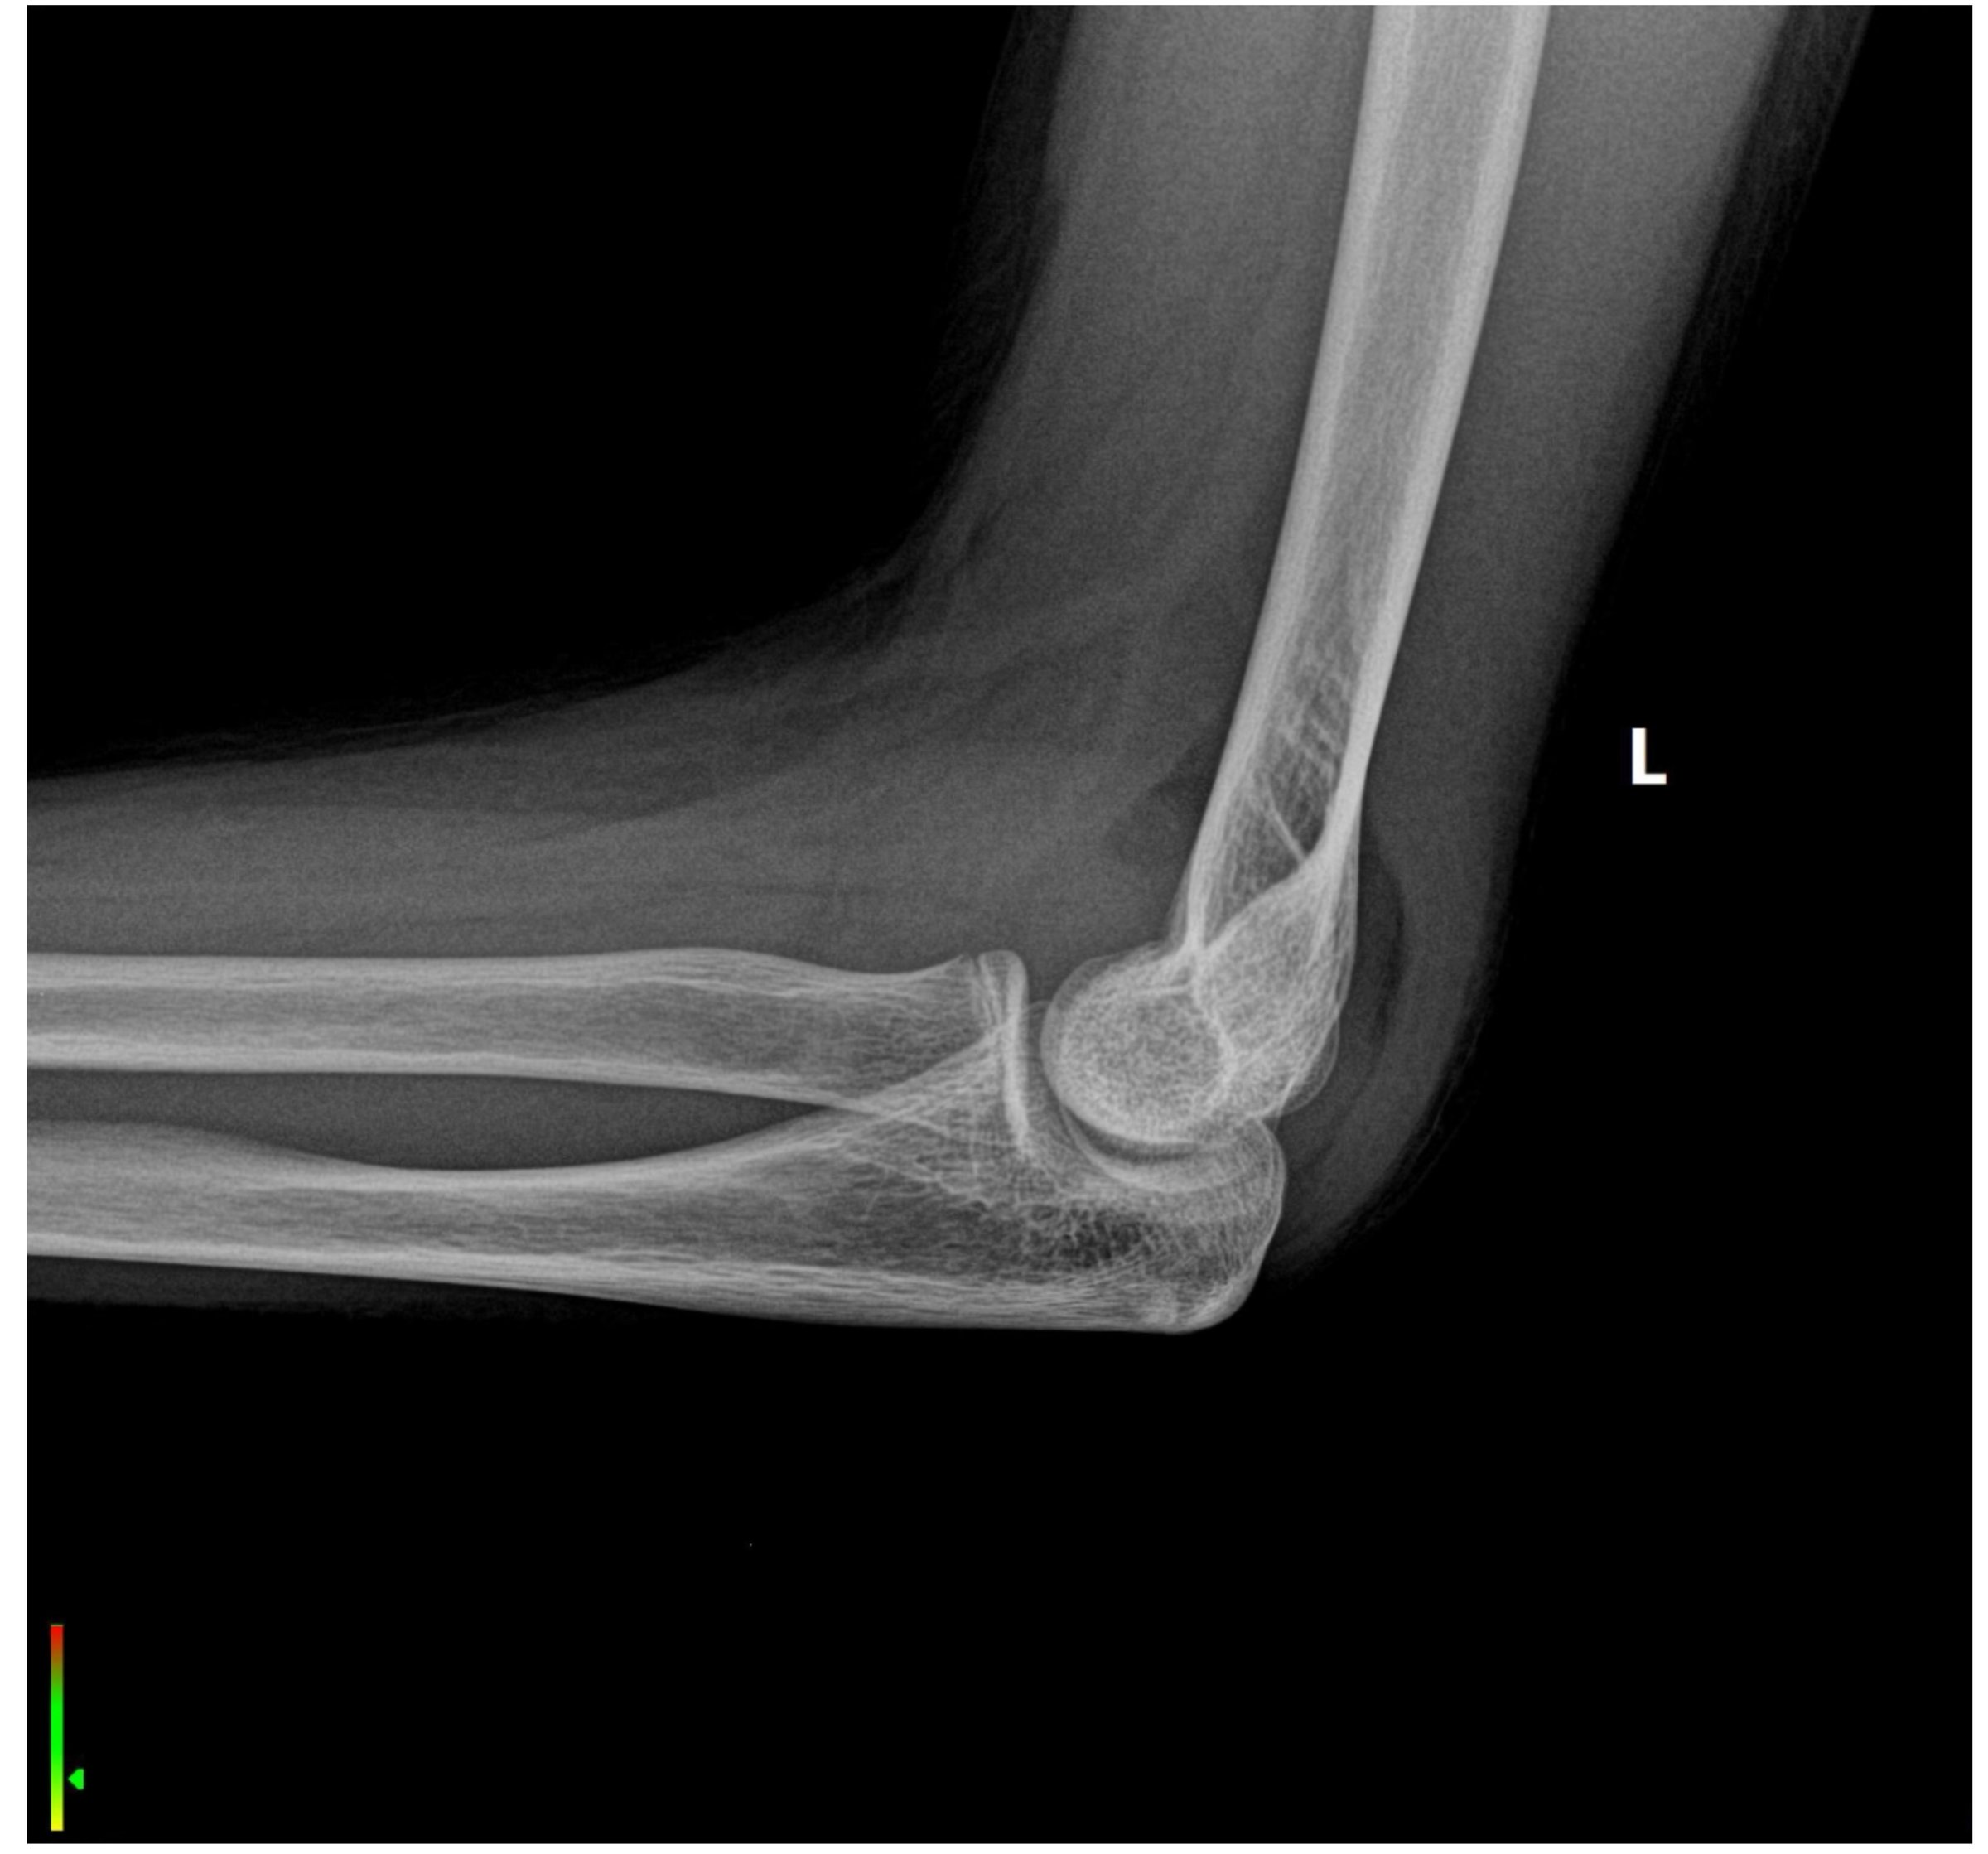

Lateral X-ray of the elbow, revealing a fracture at the elbow

Elbow fracture repair is a surgical procedure to fix broken bones in the elbow joint, including radial head fractures, olecranon fractures, and distal humerus fractures. These injuries typically result from falls, sports injuries, or direct trauma to the elbow.